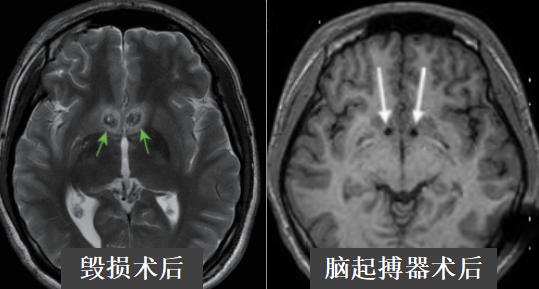

对比毁损术和脑起搏器,虽然都是手术戒毒,但却是完全相反的两个方向:前者是破坏性的,以破坏脑部成瘾神经核团伏隔核的方式阻断患者的渴求欲望;后者是修复性的,通过输入电流刺激相关神经核团,从而达到修复神经环路病变、戒除毒瘾的治疗目的。

同时,植入脑起搏器是一项神经外科常规微创手术,对脑组织没有实质性损伤,安全性有保证。目前,已经接受该治疗的所有患者没有出现因为手术造成的严重不良事件,有4名患者戒毒成功后已经全部或者部分取出了相关设备。因此,脑起搏器戒毒技术是一种可逆、可调、可控的治疗手段。